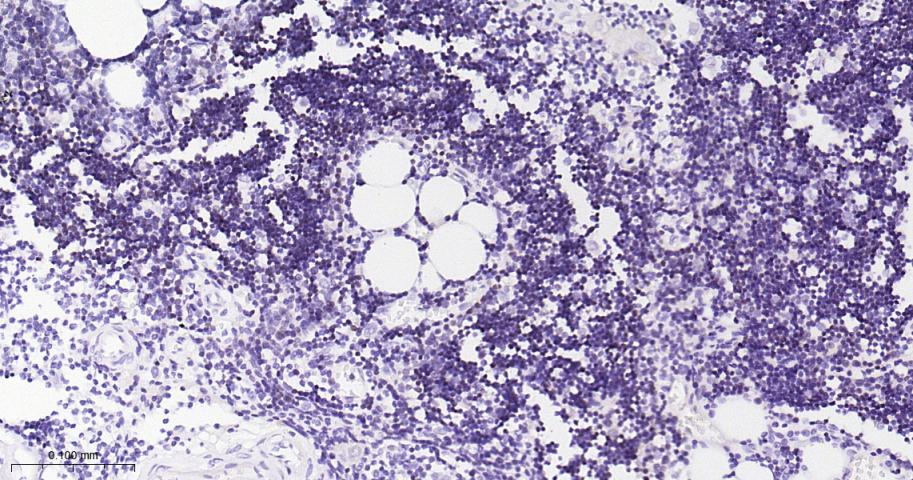

Paraformaldehyde-fixed, paraffin embedded Human Thymus; Antigen retrieval by boiling in sodium citrate buffer (pH6.0) for 15 min; Antibody incubation with GH1 Monoclonal Antibody, Unconjugated(bsm-61438R) at 1:200 overnight at 4°C, followed by conjugation to the bs-0295G-HRP and DAB (C-0010) staining.